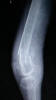

Fractura de húmero.

Fractura compleja de húmero.